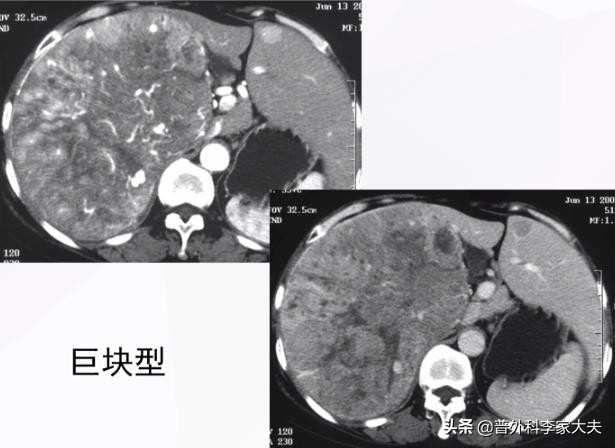

晚期巨块型肝癌